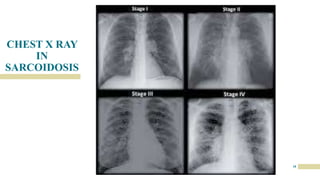

CHEST X RAY

IN

SARCOIDOSIS

17

18